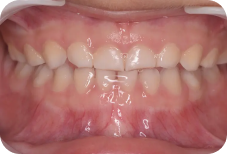

ムーシールドは受け口(反対咬合)を改善する装置です。(受け口とは下の前歯が上の前歯より前に出ている噛み合わせの事です)

主に就寝時に専用マウスピースをつける事で、舌や口腔周囲筋の状態を整え、反対咬合を改善します。

4歳から可能で、特に乳歯列期に治療を行うと、正常な顎骨の成長発育を促すことができるため、正しい永久歯の成長も期待できます。

咬み合わせが逆のまま成長すると、下顎の骨が過成長しやすい状態が続き、結果取り返しのつかないほど大きくなってしまう事もあるため、本人の負担軽減のためにも咬み合わせは早期に治しましょう。

毎晩装置をつけて寝るだけで、こんなに改善するなんて感激しています。子供にも優しく接してくださり、楽しく通院することができました。

初めは装置に対する不安もありましたが、少しずつ改善が見られ、先生方の丁寧な対応もあり、安心して通えました。